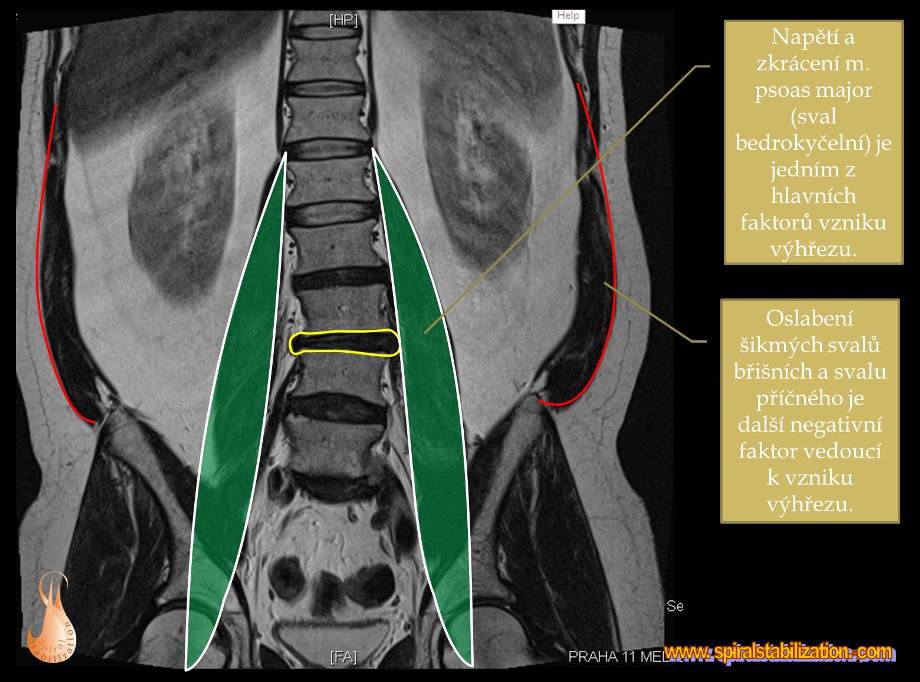

Pri dlhodobom nesprávnom držaní tela dochádza k tomu, že sa platnička nepravidelne na jednej strane deformuje. Mäkké rôsolovité jadro sa posúva mimo strednú časť, čo má za následok väčšie namáhanie a preťahovanie vlákien vo vonkajšom obale. Jadro sa časom vyklenie smerom k mieche, čím nastáva tzv. vyklenutie medzistavcovej platničky - hernia disku. Vyklenutie sa následne prejavuje bolesťou v oblasti chrbta ale nielen v nej.

Základom liečby je aktivácia šikmých brušných svalov a relaxácia chrbta.